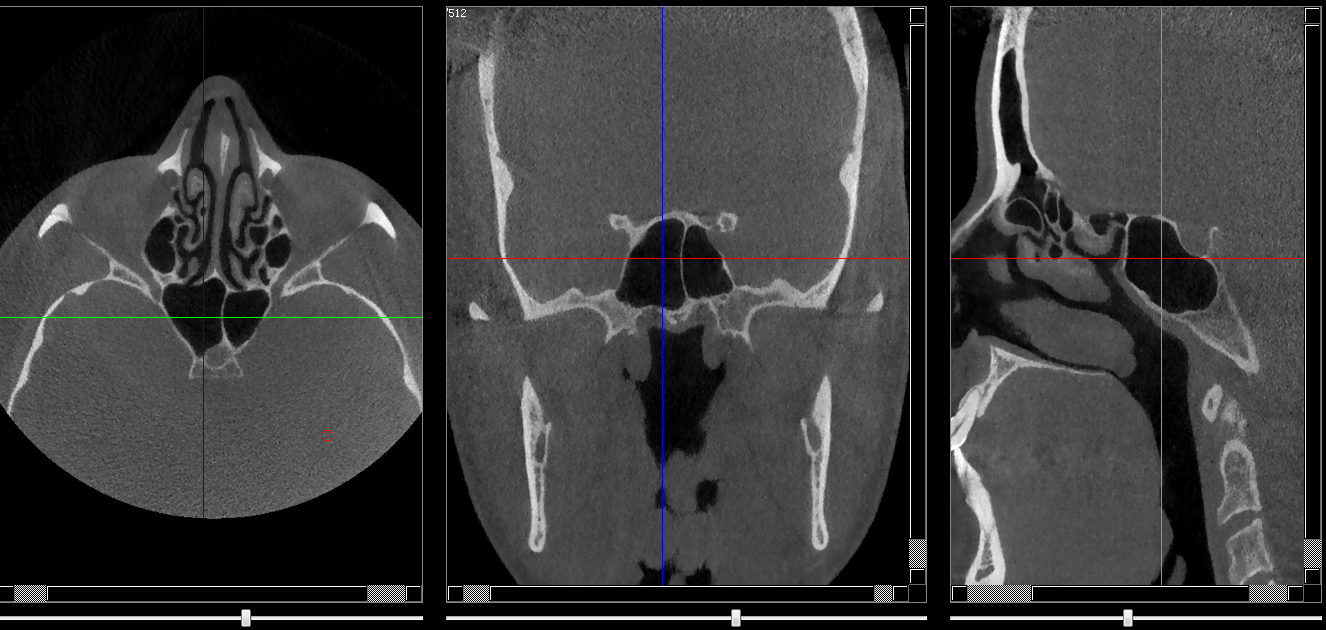

Structures osseuses

Sinus sphénoidal

Repères anatomiques

- Coupe transversale

- Début : Grande aile du sphénoide

- Fin : Processus clinoide

- Coupe frontale

- Début : Cellules éthmoidales post

- Fin : Clivus

- Coupe saggitale

- Début : Processus clinoide droit

- Fin : Processus clinoide gauche